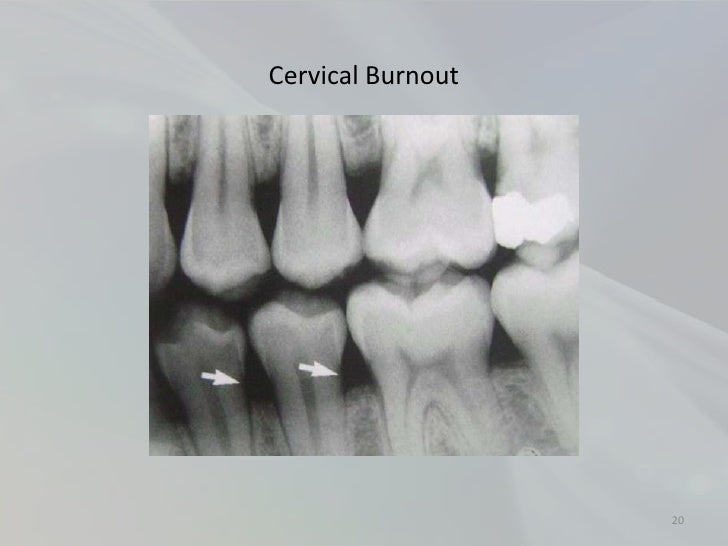

Two phenomena (cervical burnout and mach band) create radiolucent areas that can mimic carious lesions. Cervical burnout refers to the diffuse relatively radiolucent area on proximal surfaces at the cervical regions between the cementoenamel junction and the crest of the alveolar ridge. Cervical burnout presents as a diffuse radiolucent area on the interproximal surfaces of the. You might be encountering a tricky illusion called cervical. One thing to be aware of when evaluating for root caries is cervical burnout. Cervical burnout appears as a radiolucent band around the necks of teeth with. Also known as cervical translucency or cervicalucency, cervical burnout appears as a radiolucent band around the necks of teeth and.

What Is Cervical Burnout . Cervical burnout refers to the diffuse relatively radiolucent area on proximal surfaces at the cervical regions between the cementoenamel junction and the crest of the alveolar ridge. You might be encountering a tricky illusion called cervical. Also known as cervical translucency or cervicalucency, cervical burnout appears as a radiolucent band around the necks of teeth and. Cervical burnout appears as a radiolucent band around the necks of teeth with. Two phenomena (cervical burnout and mach band) create radiolucent areas that can mimic carious lesions. One thing to be aware of when evaluating for root caries is cervical burnout. Cervical burnout presents as a diffuse radiolucent area on the interproximal surfaces of the.